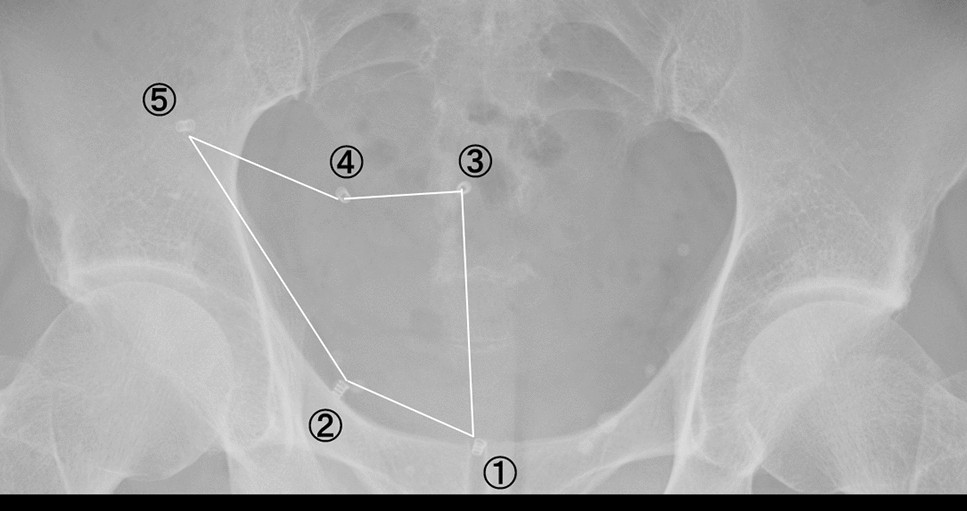

Hernia Mesh Removal | Center for Hernia Repair Dr.Iraniha placed mesh in laparoscopy inguinal hernia repair Inguinal hernia surgery - Wikipedia Inguinal Hernia Repair – GBMC Jordan Inguinal Hernia Repair With Mesh Los Angeles | Dr. Shouhed Inguinal Hernia Repair Mesh